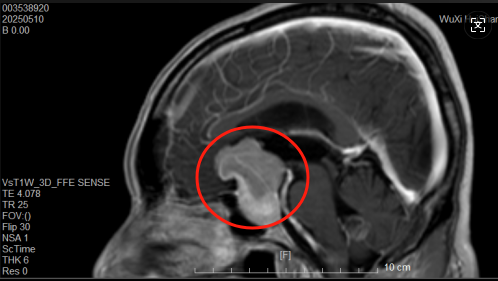

林先生(化名)长期受到垂体瘤困扰,视神经持续受到压迫,因此单眼失明、出现听力障碍,生活中遇到很多困难。

带着希望,他来到惠山区人民医院神经外科就诊。术前全面检查显示,林先生的肿瘤与视神经、颈内动脉等重要结构紧密粘连。这样的结果代表着,他的手术风险非常高,如果稍有不慎,就可能引发永久性失明或大出血等严重后果。

术前核磁共振图片